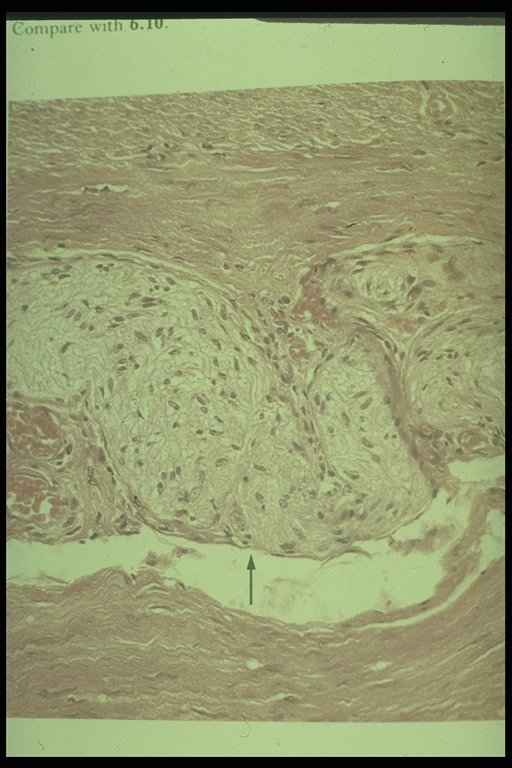

Ganglion cells (arrow) are demonstrated in normal bowel segment

Only thick nerve fiber is demonstrated without ganglion cell in Hirschsprung's disease